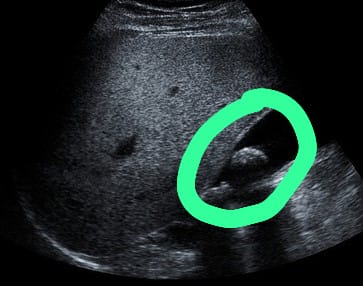

膽結(jié)石的形成與脂肪攝取有關(guān),肥胖人士是高風(fēng)險(xiǎn)群組,蕭醫(yī)生解釋:「肥胖人士膽汁中有較高膽固醇濃度及分泌,且膽固醇合成機(jī)率也較高,故容易形成結(jié)石。除此之外,懷孕婦女由於膽汁飽和度增加,加上女性荷爾蒙的生理作用及膽囊弛張性(atonic)收縮不良,易使結(jié)石情況發(fā)生。在藥物方面,長期服用避孕丸,及停經(jīng)後使用激素,臨床上發(fā)現(xiàn)有明顯較高的結(jié)石發(fā)生率。糖尿病人也易產(chǎn)生結(jié)石,一般歸因於膽汁中膽固醇分泌過多,及膽囊運(yùn)動(dòng)性不全(dyskinesia)?!鼓懡Y(jié)石沒有明顯癥狀,必須透過醫(yī)學(xué)檢查判斷是否患有膽結(jié)石,蕭醫(yī)生表示:「腹部X光檢查簡單快捷,但若膽石過於細(xì)小往往不能察覺。腹部超聲波是最常用來查看膽石的檢查,可以查看其存在、位置、膽囊有否發(fā)炎,然而若病人腹部脂肪較厚會(huì)減低檢查的準(zhǔn)確性。腹部電腦掃描或磁力共振檢查除了膽囊狀態(tài),也可檢查腹部內(nèi)各個(gè)器官,準(zhǔn)確性不受病人體形影響。內(nèi)視鏡超聲波可以確認(rèn)膽石位置以及膽囊膽管狀態(tài),不過具有入侵性風(fēng)險(xiǎn),必須經(jīng)過專科醫(yī)生評(píng)估,有需要才安排進(jìn)行?!?/p>